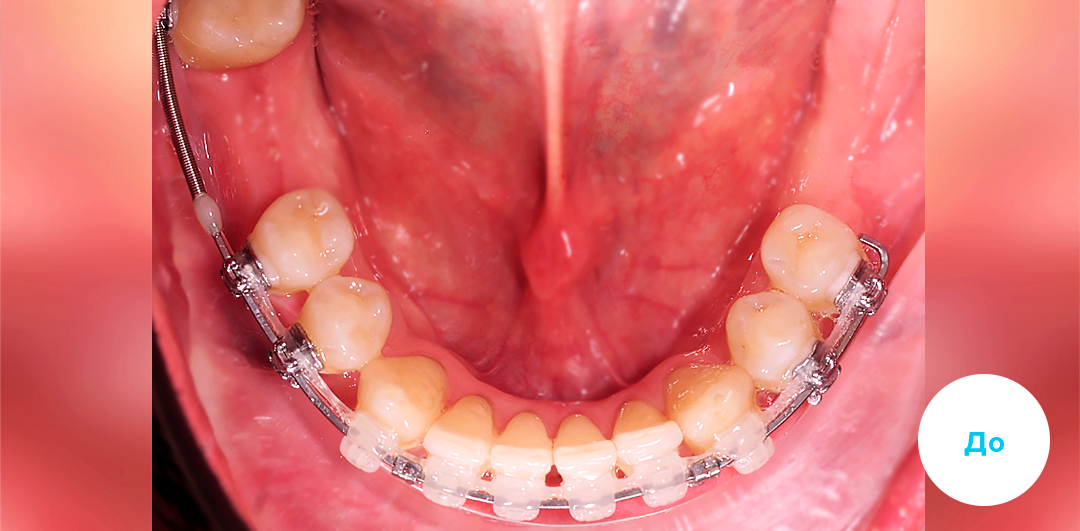

Результаты лечения